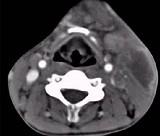

男性,67岁,颈部出现疼痛性肿块半年余,CT扫描如图所示,最可能的诊断是()A.神经鞘瘤B.囊肿C.淋巴结核D.淋巴瘤E.血管瘤

问题 男性,67岁,颈部出现疼痛性肿块半年余,CT扫描如图所示,最可能的诊断是()

选项 A.神经鞘瘤 B.囊肿 C.淋巴结核 D.淋巴瘤 E.血管瘤

答案 D